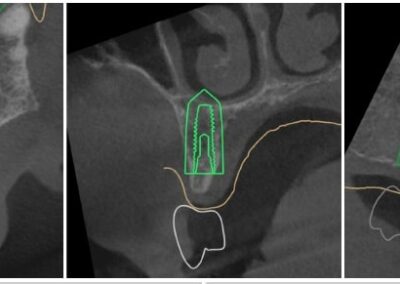

We start with a comprehensive full mouth examination, digital X-rays, a dental 3D(CBCT) scan and Trios5 Scan. The scanned images provide high-resolution images in a three dimensional plane. We use these images and scans for precise treatment planning.

CBCT 3D Scan

Using the 3D images in special planning software, the Dentist maps out the exact position and angle of insertion of each implant. They take care to place implants where they will be stable and in the best position to support the replacement teeth. They will also plan out any bone grafting (if needed) to ensure the implants have strong bone support.